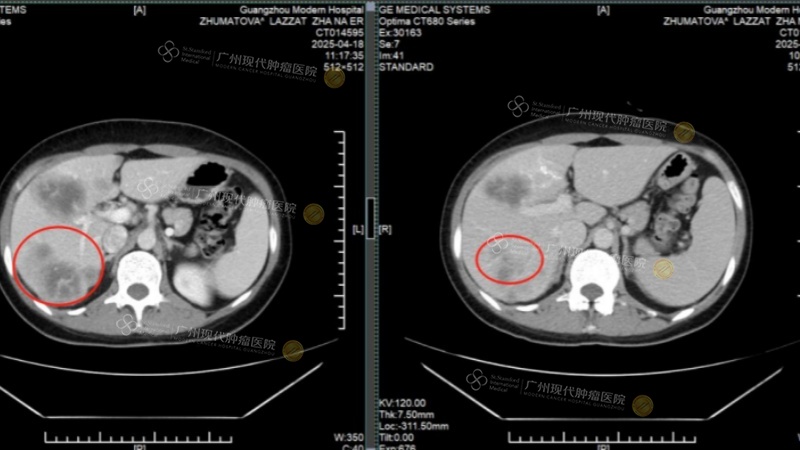

In April 2025, accompanied by her sister, LAZZAT arrived at our hospital and underwent a full-body examination. CT results showed a left breast mass approximately 2×1cm in size, multiple liver metastases with the largest nodule over 4cm in diameter, and liver function already impaired by the tumors.

[Liver Metastases: Before Treatment vs. After Treatment - Tumors Mostly Gone]

After two courses of treatment, LAZZAT's breast tumor was completely inactivated and had disappeared upon re-examination. The liver metastases had shrunk by more than half, her liver function indicators returned to normal, and tumor markers CEA and CA153 levels dropped significantly. Thanks to the meticulous care of the medical staff, her liver function improved, her feelings of fatigue and weakness markedly decreased, and she felt a long-lost sense of vitality.